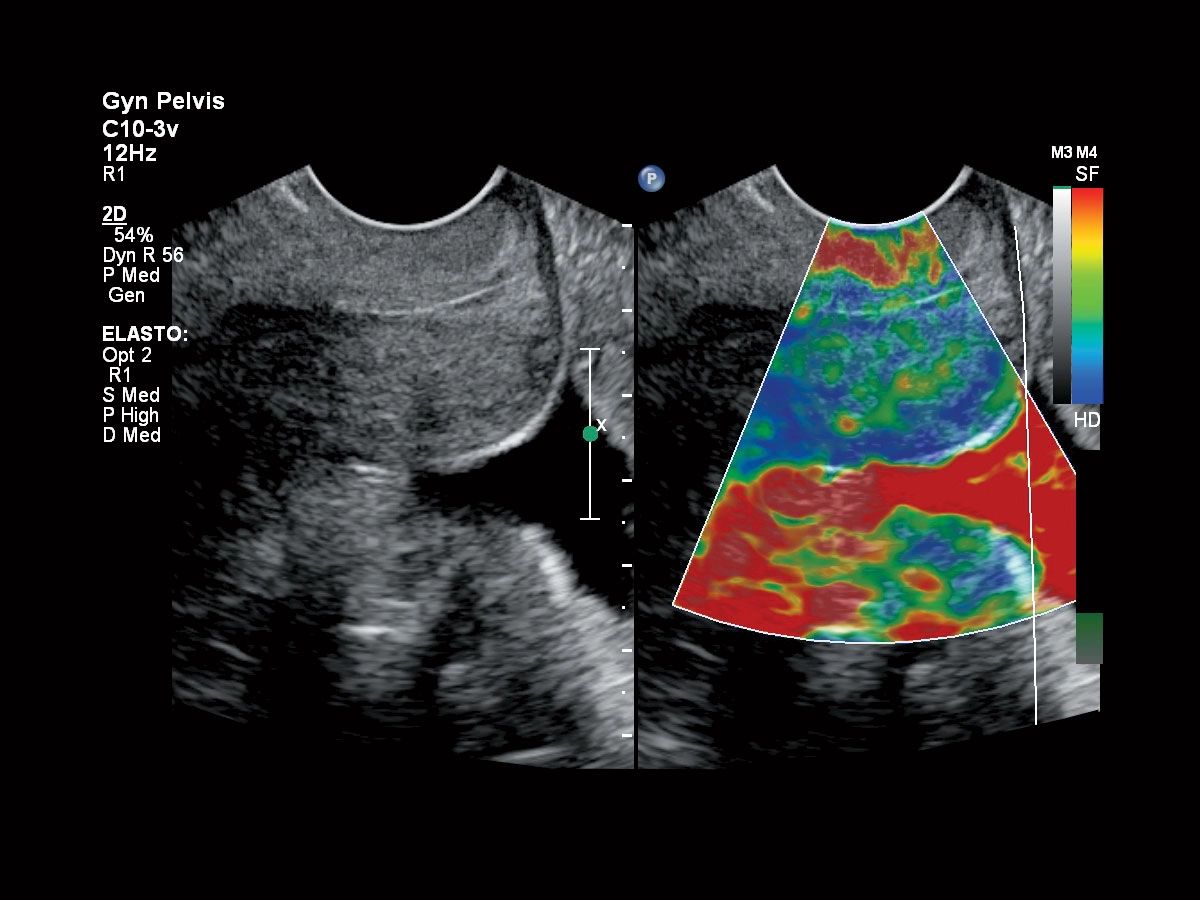

Исследования в онкологии

- Contrast GI - идеальная визуализация контрастных веществ

- Strain Elastography - эластография

- Эластография сдвиговой волной для оценки состояния печени

- Дифференциация тканей у пациентов разных категорий

- Компрессионная эластография для молочной железы и органов малого таза